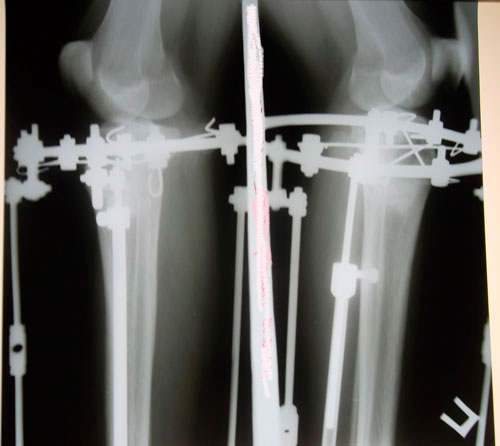

Всем привет.выложили наши фотографии когда я увидела свои ножки мне они не понравились как будто правая иксит а левая прямая.НН сказал что обе идеально ровные по рентгеновскому снимку.но вчера когда присмотрелась еще раз показались не симетричными вобщем настроения нет

Русалка, здравствуйте! Зря вы переживаете! Я как только на фото глянула, сразу в голове мысль - идеально симметричные, пропорциональные, ровные!!! Обе абсолютно одинаковые. Поздравляю вас, желаю скорейшего выздоровления и восстановления!rusalka писал(а):Всем привет.выложили наши фотографии когда я увидела свои ножки мне они не понравились как будто правая иксит а левая прямая.НН сказал что обе идеально ровные по рентгеновскому снимку.но вчера когда присмотрелась еще раз показались не симетричными вобщем настроения нет

Всем доброго вечера.сегодня приходил КН.а вообще он кажды день приходит интересуется как наши успехи.мы говорим ему все о своих болячках.очень тщательно всегда выслушает посмотрит и улыбнется если надо назначит лекарства.сегодня я сказала о своих ногах он еще раз посмотрел и сказал что у меня даже левая иксит о которой я так переживаю т.е у меня легкий икс.ему виднее.ведь он в етой области спец.переживать думаю нечего.ведь НН если говорит что все значит все.все долой хандра и плохое настроение.

Привет, Русалочка. Что за хандра??? Ноги получились СУПЕР!!! Лучше не бывает. Это говорит и НН, это показывает и рентген. Может переживаешь, что НН уехал? Так тебе же легче всего. Живешь недалеко. Приехал, подкрутил и все дела. А если совсем не нравится, можно вернуть исходник. (Шучу). Долой плохое настроение и вперед за новыми изменениями. Я, например, жду снятие и все для того, чтоб пойти и приобрести мини платья, обтягивающие шорты, лосины и все то, что я не могла купить из-за своих кривоножек. Сейчас самое главное - это быстрое сращение костей и образование костной мозоли. Так, что давай живи и радуйся тому что, до исполнения мечты осталось совсем чуть-чуть

Дата операции 19.07.2013г.

Дата снятия аппаратов 30.10.2013г.

Срок лечения 101 день.